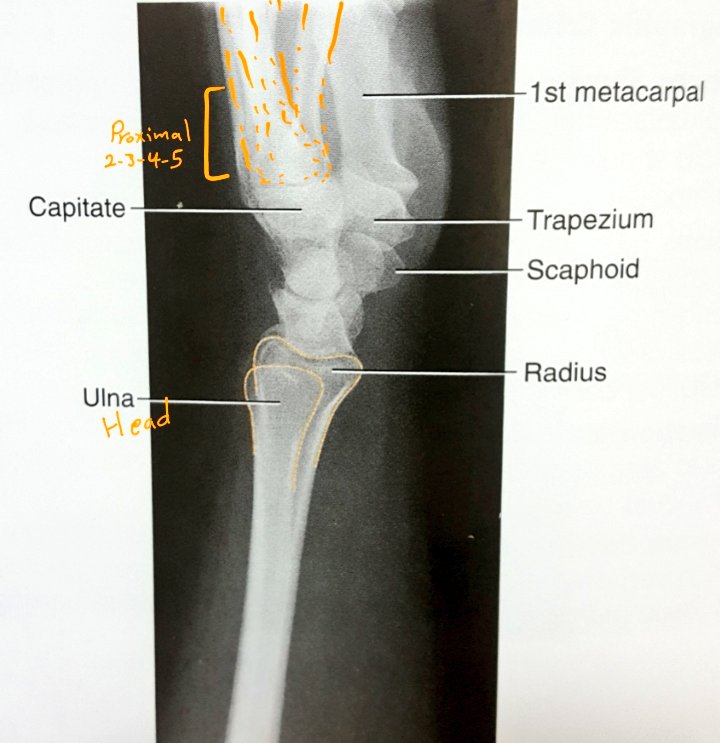

☆ الرسغ

☆PA wrist

يتكون من ٨ عظيمات : ٤في الصف الأمامي و ٤ في الصف الخلفي.

▪الوضع:

•يجب أن يكون الكتف و العضد و الذراع و اليد على مستوى واحد برفع الكاسيت او خفض المريض(حتى يكون التصاق الرسغ كامل)

•يقوم بثني المرفق ٩٠°.

•يقوم بجعل الذراع و اليد على استقامة واحدة.

•من المهم أن يقبض الأصابع ليزيد من التصاق الرسغ.

السنتر: على الرسغ مباشرة.

لابد أن تشمل الصورة

Mid/Proximal metacarpals

Distal radius and ulna

كيف نعرف أن الوضع تم تطبيقه باحترافيه ولا يوجد ميلان؟

•وجود التقوس concavity shapes

على جانبي metacarpals.

•تباعد نهاية عظمتي radius&ulna

ويسمح بوجود تراكب بسيط في المفصل بينهما.